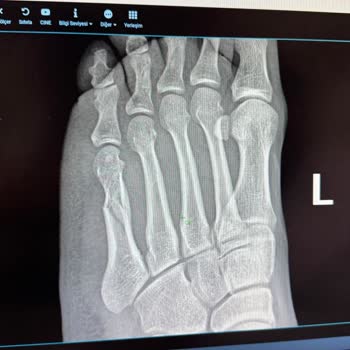

Beylikdüzü Medicana Hastanesi gerçekten çok ama çok kötü bir hastane. 12.06.2025 tarihinde, yani dün, ayağım kırıldığı için hastaneye gitmek zorunda kaldım. Acil olmasına rağmen hemşiresinden çalışanlarına kadar herkes ilgisiz ve bilgisizdi.

Ayağımın röntgeni çekildi, ardından atel yapılacağı söylendi. Tam 2 saat boyunca acı içinde kıvranarak doktorun gelmesini bekledim; meğerse doktora haber vermemişler. Doktor geldiğinde, 'Neden 10 dakika önce haber verdiniz?' diye kızdı ama hiçbir hemşire ve çalışan sorumluluğu üzerine almadı.

Tepki gösterince S*** isimli hemşire benimle ilgilenmedi. Böyle bir hastanede mağdur oldum. Başka insanların mağdur olmaması için buraya yazıyorum; paranızla rezil oluyorsunuz. Ayrıca benden atel ve röntgen işlemi için 22 bin TL'den fazla para aldılar.

Ayağım yere basamaması sonucu tekerlekli sandalye talebinde bulundum yarım saat bekletildim sonra Ayağımın röntgeni çekildi sonra Atel yapılacak denildi acil bölümünde tam 2 saat Atel yapacak doktorun gelmesini bekledim acı içinde kıvranarak ; meğerse doktora haber vermemişler doktor geldi niye 10 dakika önce haber verdiniz diye orada çalışan Firdevs isimli çalışana ve ( sıla isimli olduğunu şifahen öğrendiğim hemşire kendi adını söylemek istemedi bana şikayet edeceğim dediğim için ) hemşireye kızdı hemşire kendi adını söylemek istemedi bana şikayet edeceğim dediğim için ama hiçbir hemşire ve çalışan görevli sorumluluğu üzerine almadı. Bende tepki gösterince sıla isimli hemşire benimle tartışarak inkar etti ve daha sonra benimle kasıtlı olarak çünkü tek hemşire orada o vardı sorularıma dahi cevap bile vermedi ilgilenmedi düşünebiliyor musunuz? Böyle saçma bir hastane görmedim hem de Medicana grubunda böyle bir hastane ve çalışanları asla ama asla kabul edilemez siz siz olun sakın ama sakın gitmeyin paranız ile rezil oluyorsunuz ve benden Atel röntgen işlemi için ve de yatak parası olarak 22 bin tl den fazla para almışlar sigortamdan haram olsun

Özellikle isimlileri yoktu ve sorduğumda da söylemeyen Firdevs ve sıla isimli çalışanlardan Sıla isimli hemşire ve Firdevs isimli çalışan kişilerden şikayetçiyim tam 2 saatten fazla gereksiz yere ayağım kırık bir şekilde bekletildim ve hiçbir şekilde benimle ilgilenilmedi ve tabiri caize param ile rezil oldum çektiğim acı da cabası oldu 17.40 da girdiğim hastaneden 21.30 da çıkabildim gerisini siz düşünün